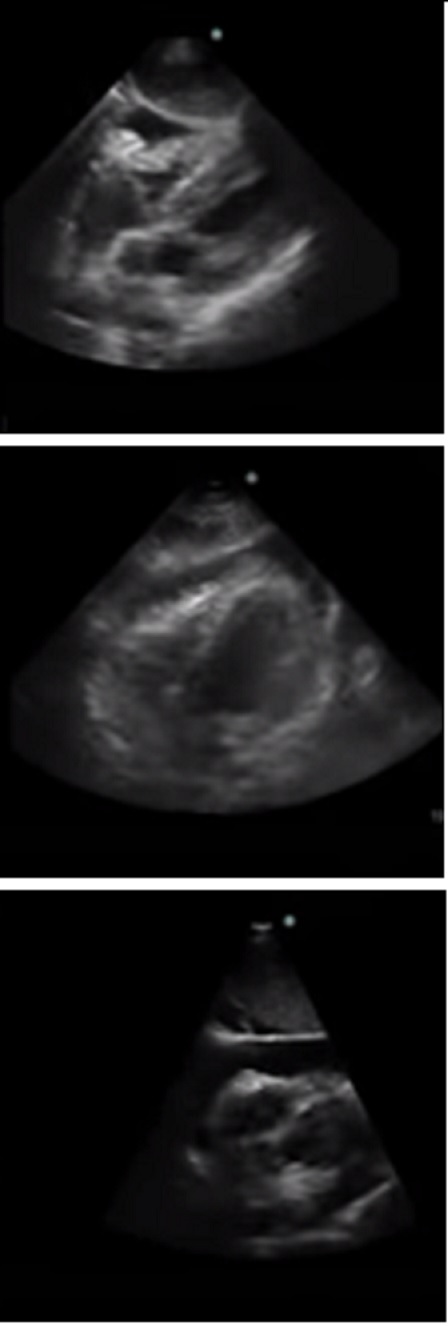

Heart Subcostal Pericardial Effusion Examples Image